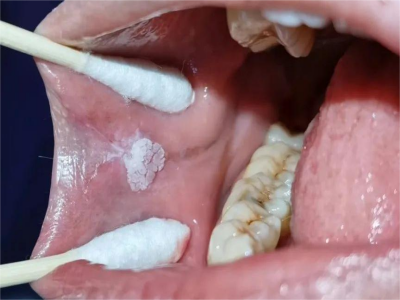

牙龈

白斑

口腔白斑病牙龈块状白斑图

口腔白斑病表现为牙龈处有稍高出黏膜表面的白色斑块,不粗糙、柔软,周围黏膜正常,患者无明显的自觉症状,偶尔有粗糙感或木涩感。